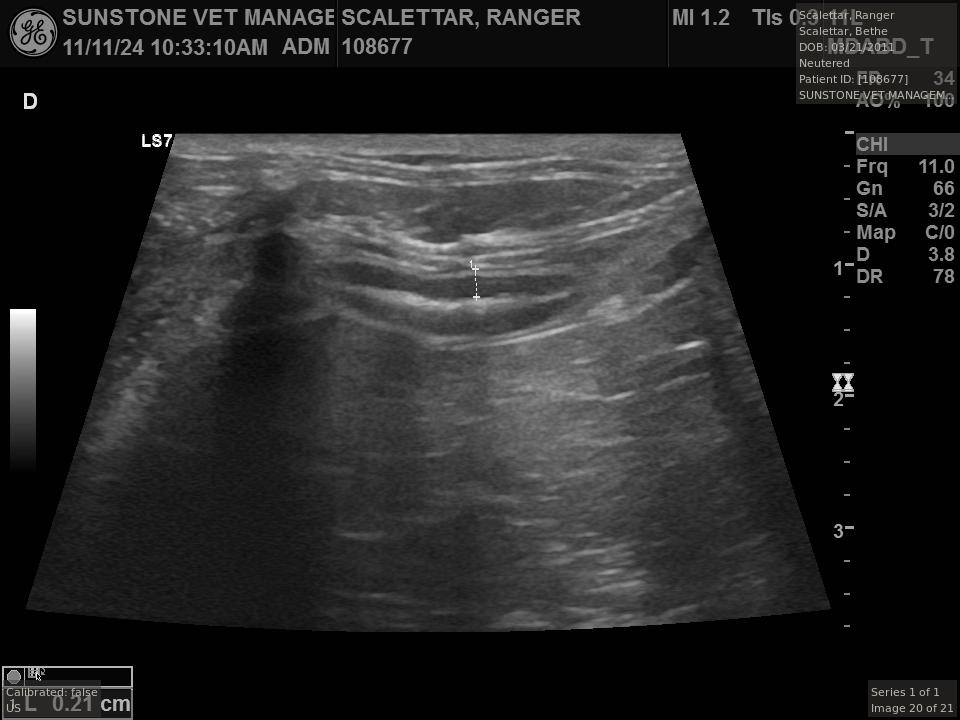

The veterinarian generated a series of images showing different organs and substructures by

changing the position and orientation of the ultrasound transducer. The images were collected

in a defined order, which is repeated from patient to patient, ensuring that nothing is missed. In

Ranger's case, the sonographer collected about twenty images during an examination that

lasted about fifteen minutes.

The sonographer stated that Ranger's ultrasound images were largely normal for an older cat. In particular, they show changes in the kidneys that are commonly noted in geriatric cats and that reflect a risk for the development of chronic kidney disease. However, the images did not show any significant abnormalities in Ranger's stomach, intestines, and associated lymph nodes. Nonetheless, the results did not rule out recurrence of Ranger's small cell lymphoma.